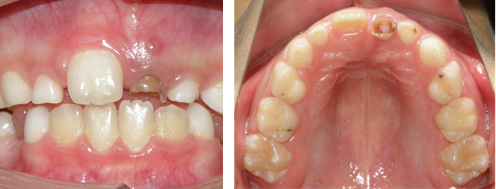

Al realizar el examen clínico, se observó ausencia del Organo Dental 21OD 21, en su lugar persistencia del OD 61 con destrucción coronaria y pólipo pulpar. Además, se identificó fístula en encía adherida vestibular a nivel de este mismo órgano dentario. Su contralateral OD 11 se observó totalmente erupcionado sin alteraciones (Figura 1). En el examen radiográfico se evidenció la presencia del OD 21 incluído, en un estadio de desarrollo de Nolla 8, ubicado en posición vertical y presencia del 61, el cual persiste en su posición conservando al menos un tercio de su raíz. No se observó fractura u otro tipo de afección al diente permanente (Figura 2).

Figura 1. Fotografías intraorales iniciales. Se observa OD 61 persistente con fractura coronal y fistula a la altura del ápice.